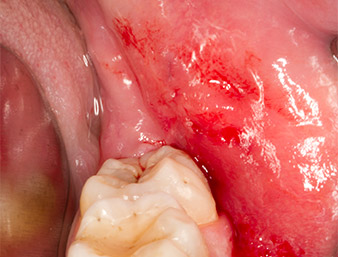

Subsequently, the autogenous bone tissue (Fig. 13) was placed into the alveole and the surrounding bone defect (Fig. 14). Collagen fleece covered the bone chips up to bone level as protection for the exposed nerve (Fig. 15). Sutures using vicryl thread, USP 4.0, were used to close the opened up soft tissue (Fig. 16). An Ibuprofen preparation (Seractil 400 mg, 3x1) and an antibiotic consisting of amoxicillin and clavulanic acid (Augmentin 1 g, 2x1) were prescribed postoperatively.

The wound healed without complications (Fig. 17) and the sutures were removed after seven days. The patient reported the return of proper sensitivity. There was no longer any pain.

sutures (vicryl thread 4.0)

Fig. 16: The wound region is closed with sutures (vicryl thread 4.0).

Condition after removal of sutures

Fig. 17: Condition after removal of sutures 7 days after extraction: Wound healing progresses without complications. Paraesthesia, present after the initial osteotomy, has healed; pain no longer present.